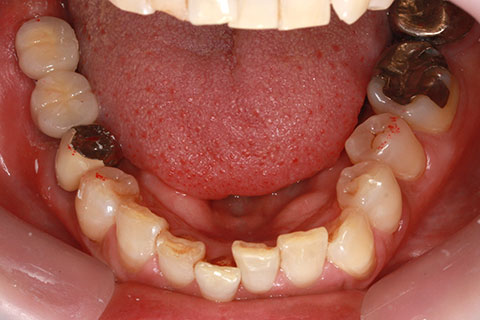

症例3

治療前

インプラント埋入時

治療後

- 年齢・性別

- 60歳男性

- 治療期間

- 2ヶ月

- 抜歯

- なし

- 治療費

- 61.6万円

- 備考

- 右下6.7欠損

- 治療内容

- 右下6.7欠損部にインプラント埋入

- 施術の副作用(リスク)

- オペによる知覚障害。インプラントによる歯肉炎。インプラント脱落。